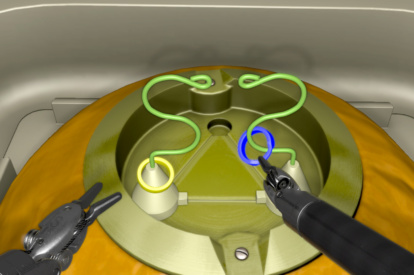

Robotic basic tasks modules allow the user to familiarize with and master the fundamental aspects of robotic skills, while clinical procedure modules let surgeons immerse themselves into partial or entire robotic virtual procedures.

Get a glimpse of the exercises included in the RobotiX Mentor, from the fundamental aspects of instrument manipulation to a variety of full procedures.

Robotic Suturing Module

Stapler Module